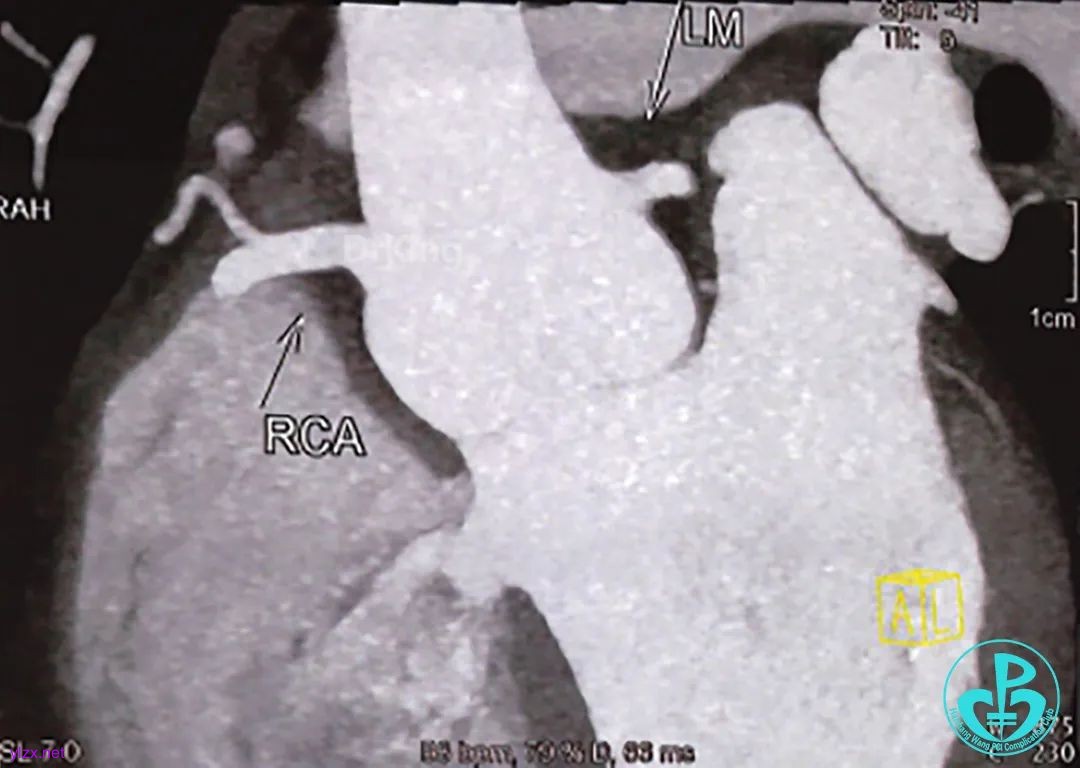

术前CT全方位判断室缺位置、形态及大小: